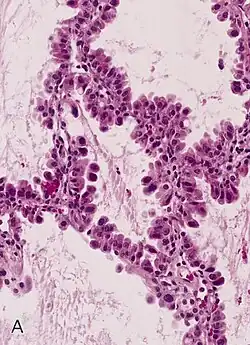

Tinción y montaje

El método de tinción de rutina es el denominado como hematoxilina-eosina (H-E). La hematoxilina es un colorante nuclear, y la eosina, citoplasmático. También existen las denominadas técnicas especiales, tal como: Gomori (para fibras de reticulina), Ziehl Neelsen (para bacilos ácido-alcohol resistentes), Grocott (para hongos), orceína (para fibras elásticas), Gordon-Sweet, rojo Sudán, negro Sudán, azul de Nilo, Golgi, etc.

Técnica de hematoxilina-eosina